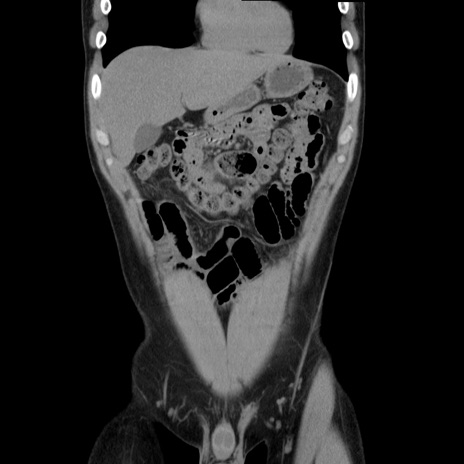

症例36(冠状断像)

【症例】20歳代 男性

【主訴】心窩部痛

【現病歴】今朝より上腹部痛あり。一旦軽快していたが再度出現したため救急要請。昨日夕に白身の魚を含む刺身を食べた。

【身体所見】BP 136/89mmHg、HR 74/min、BT 37.0℃、腹部:膨満、軟、心窩部に圧痛あり。反跳痛なし、筋性防御なし、腸雑音やや亢進あり。

【データ】WBC 17700、CRP 0.48